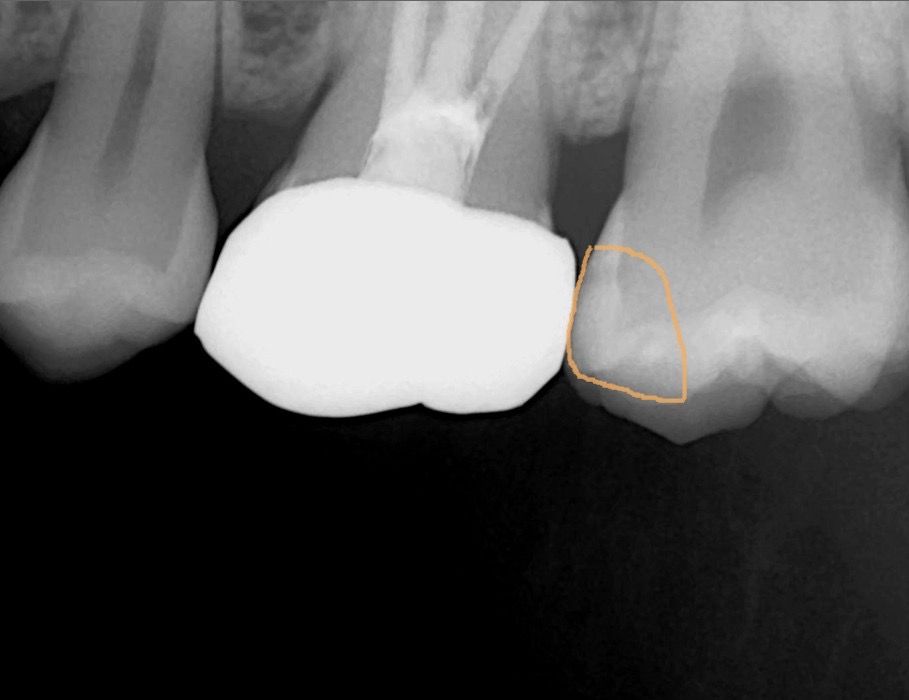

엑스레이사진입니다. 노란동그라미친부분이 충치인지 알수있을까요? 치과마다 충치갯수를 다르게 이야기해줘서 너무헷갈리네요 ㅜㅜ

• 1번 째 사진

사진으로 봤을 경우에는 충치가 있어 보이진 않습니다. 하지만 육안으로도 확인을 해야 할 수 있기 때문에 정확한 확인을 위해서 저는 치과에서 진료를 받아보는 것이 좋습니다.

엑스레이 상으로는 충치가 잇는것처럼 보이긴합니다. 작은 엑스레이를 찍어보면 더 정확히 알수잇을것같고, 충치가 의심이 되긴합니다.

에긋레이 사진에서 봤을땐 특별히 충치의 양상은 없습니다. 다만, 충치는 엑스레이 사진만으로 진단 내리기에는 부족함이 있을 수도 있습니다.